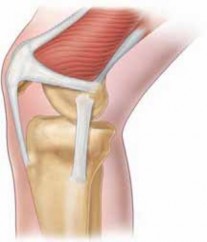

Proximal Realignment of the Medial Patellofemoral Ligament DEFINITION In most cases, patellar dislocation res…